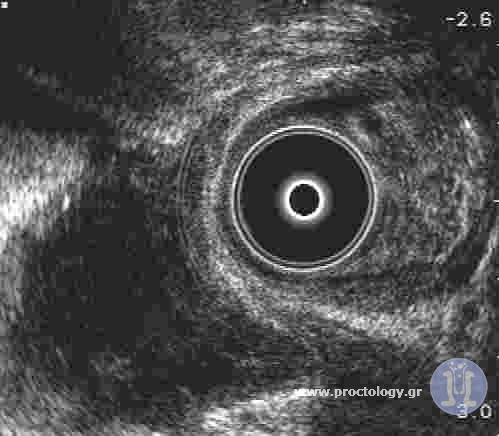

Rectoanal ultrasonography represents a significant advancement in the diagnostic approach and investigation of lesion extent within the anorectal canal. This … More